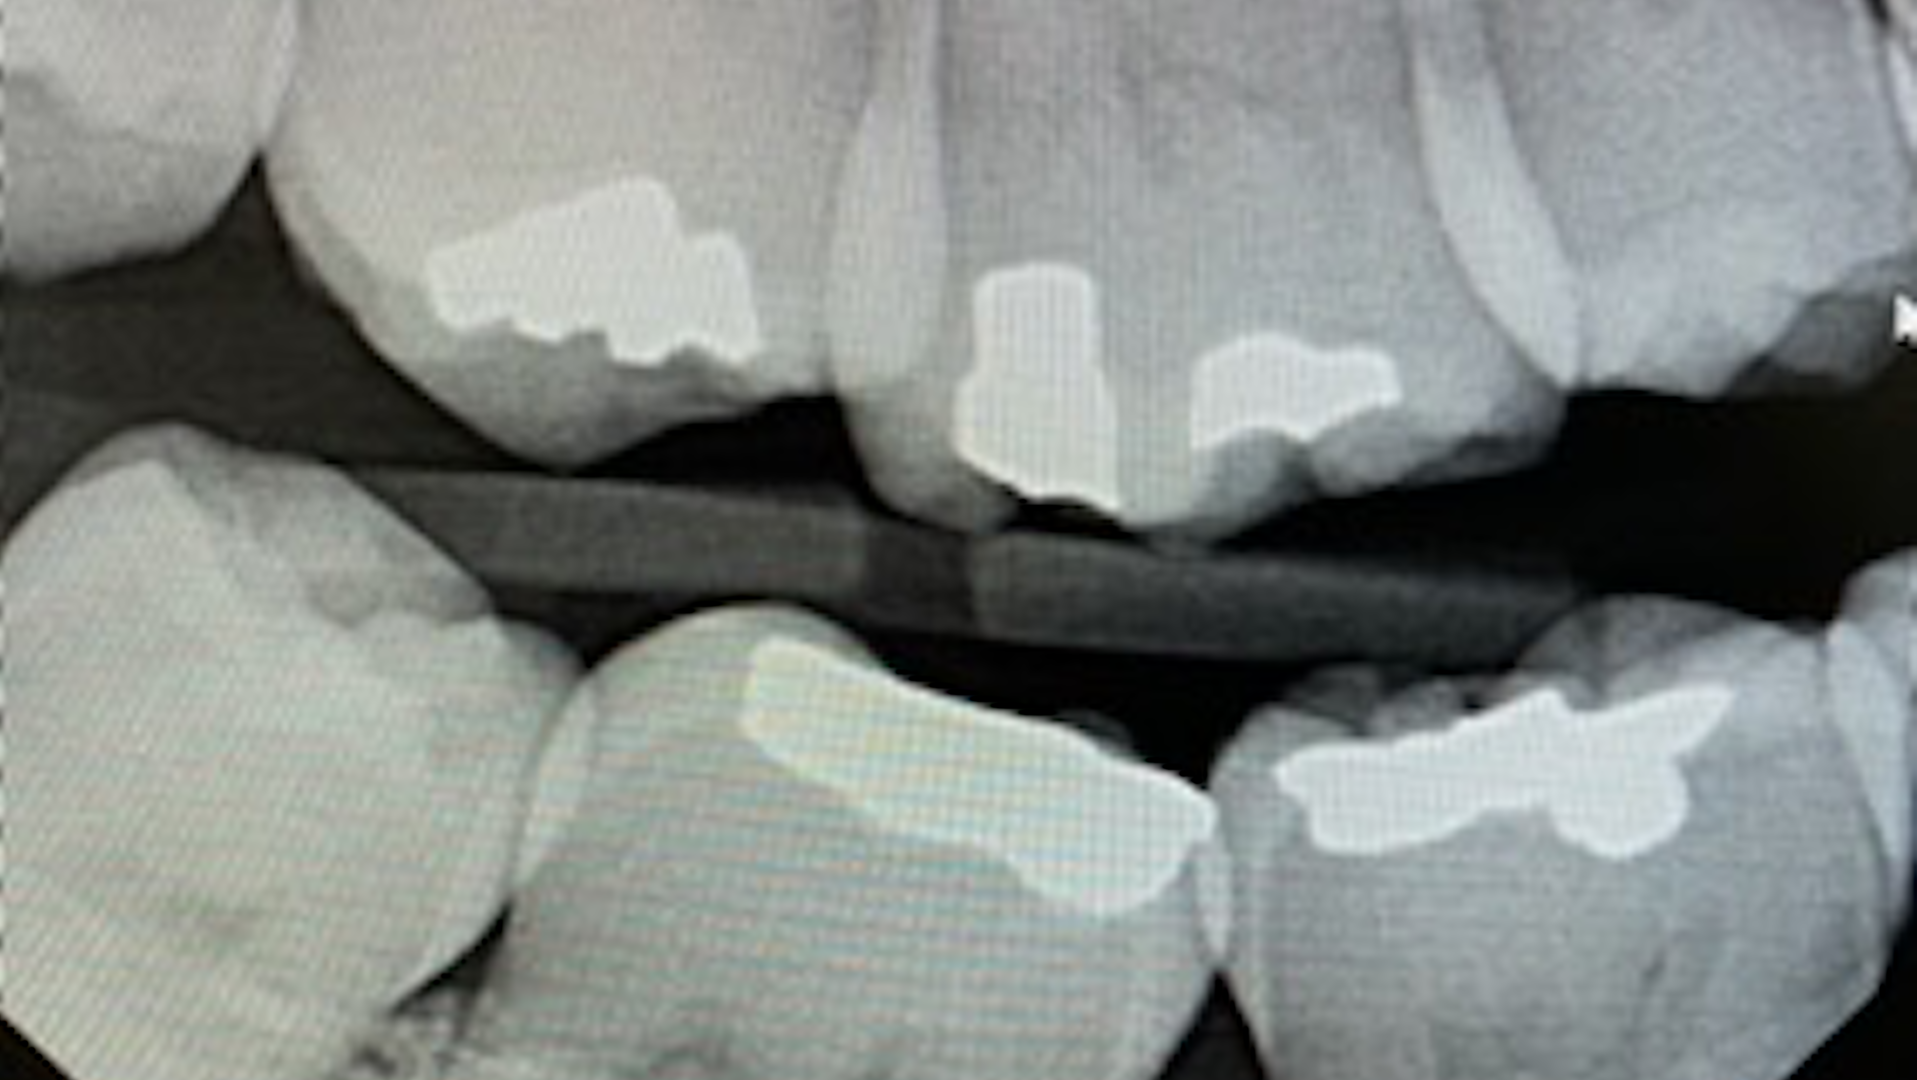

Literature suggests using the “open-door method” when contacts need to be clear and diagnostic.5 This method is achieved by moving the sensor distomesially by 15 degrees to ensure the canine is visible. This will keep the interproximal spaces open in the premolar bitewing. To avoid horizontal overlap, the central ray should be perpendicular to the arch of the teeth and directly through the interproximal spaces. With proper training and education on the concepts to mitigate overlapping, we can avoid exposing our patients to unnecessary radiation. Unfortunately, because the angle of the PID is off in Figure 1, the patient will need to be exposed to another radiograph. Proper angulation is shown in Figure 2, and proper positioning of the open-door method is shown in Figure 3.

“Horizontal angulation refers to the positioning of the PID and the direction of the central ray in a horizontal, or side to side, plane.”6 Paralleling, bisecting, and bitewings all use similar principles of horizontal angulation and will not change according to technique. The PID needs be directed toward the center of the ring using a horizontal/parallel technique. With this correct angulation, proximal spaces will be cleared, and the radiopaque enamel with either be just touching or have a distant radiolucent line of separation. This will produce a diagnostic image (figure 4) where calculus or caries lesions will not go undetected.